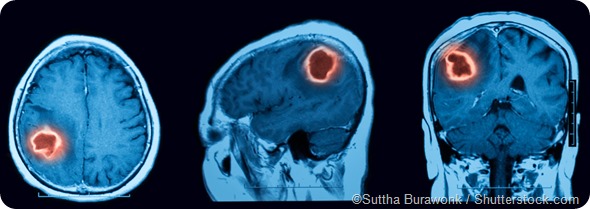

MRI scan cerebral hemorrhage

When symptoms of ICH are observed, neuroimaging should be carried out as quickly as possible - usually CT or MRI are performed. A lumbar puncture or CT angiography may also be necessary to confirm the diagnosis. Treatments include supportive care, reversal of anticoagulation therapy and surgical evacuation.